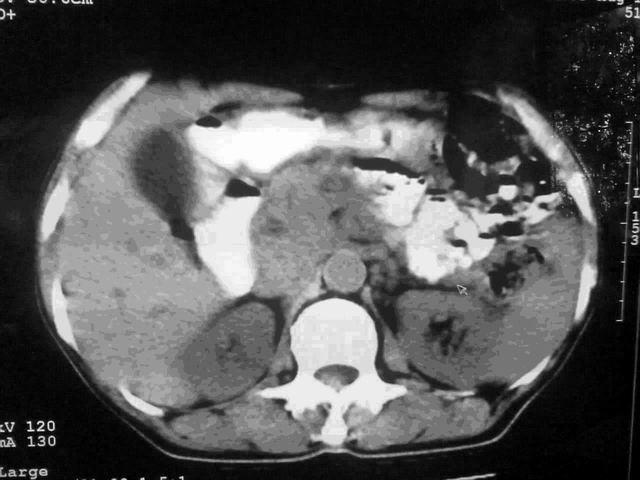

我这个考考大家眼力,看看是升结肠ca还是降结肠ca

好象是横结肠占位肝转移,胰头占位?【伙计,您的片也真够意思】

伪影太多,考虑降结肠癌伴肝转移,胆囊炎

伪影太多,考虑升结肠癌伴肝转移,胆囊炎

胰头占位?

考虑升结肠癌伴肝转移;胆囊炎。

结肠占位并肝及腹膜后淋巴结转移。

明确考眼力!考虑降结肠癌伴肝转移可能性。

考虑升结肠癌伴肝转移;胆囊炎